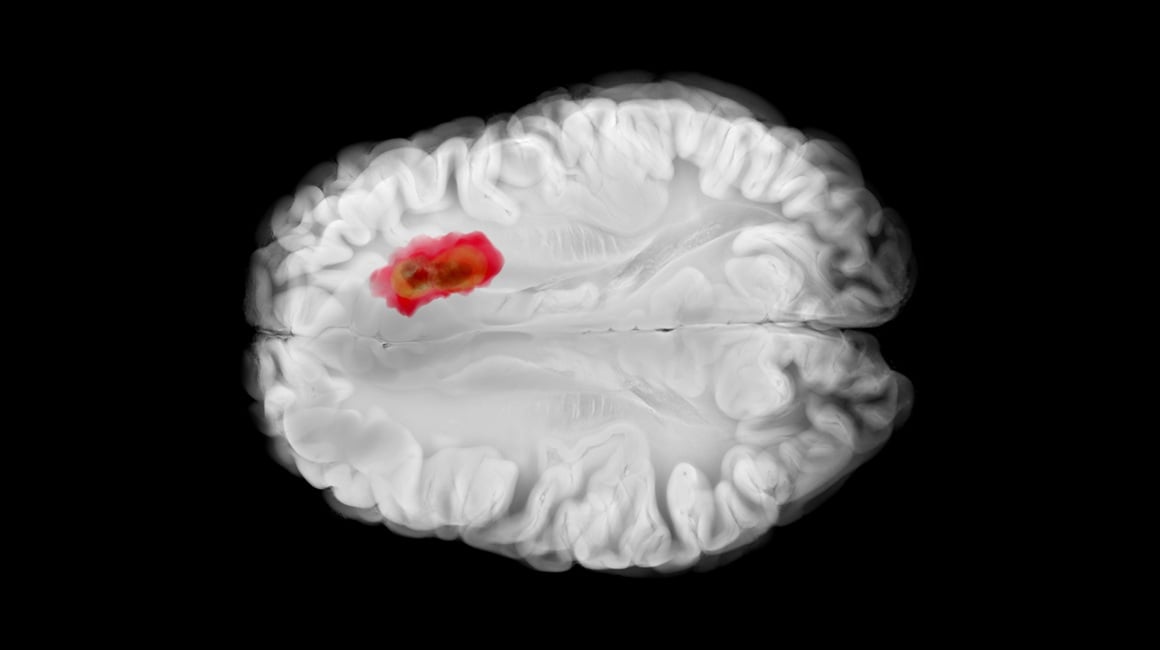

Otkrivši tko je glavna “meta” hidralazina, istraživači su analizirali njegov utjecaj na glioblastom – tumor koji se ranije već povezivao s visokom ADO aktivnošću.

Glioblastom je izuzetno agresivan tumor s vrlo lošom prognozom – prosječno preživljenje iznosi 12 – 18 mjeseci, a petogodišnja stopa preživljenja tek oko 5 %.